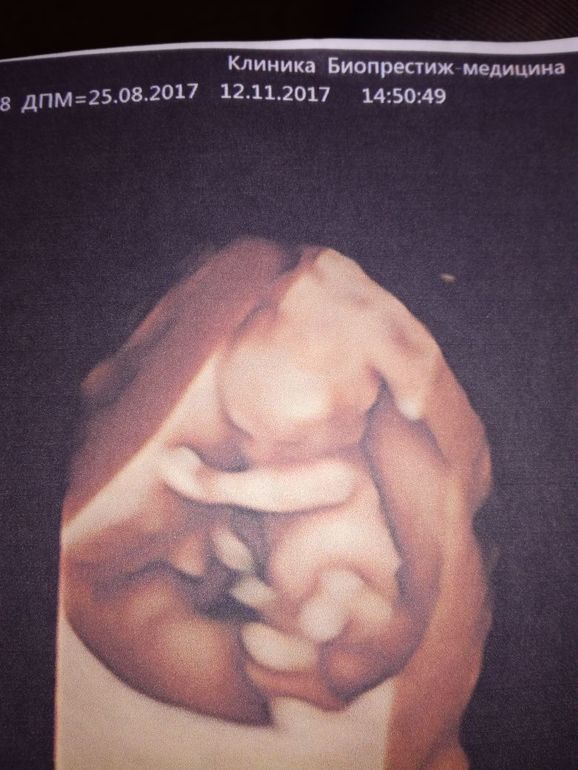

УЗИ, КТГ, доплерКакой сегодня волнительный день , свои // я впервые увидела 15.09 и мне кажется эти два месяца ожидания скрининга-были вечностью. Хорошо, что у Инвитро есть возможность послушать сердцебиение за 150 р и я бегала периодически на свидания с малышом, просто не могла по-другому держать себя в руках. Этот вечный мондраж и трясучка. Сегодня ровно 11+2, мы поехали с мужем на платный скрининг, на 3д УЗИ к Пятых. Это конечно что-то потрясающее, огромный экран, где видно каждый пальчик. Предстоит еще и бесплатный скрининг в 13 недель, от него не отвертеться, но там не пускают мужа, не дают фото, поэтому мы сделали свой собственный скрининг чуть-чуть пораньше. Малыш уже настоящий маленький человечек! Сначала он спал и прикрывал носик рукой, но потом его разбудили и он начал так активно танцевать в животе, это непередаваемые ощущения, он там внутри живой, такой родной и долгожданный!

Результат крови будет завтра. Надеюсь там все хорошо.Пугает низкая плацентация. У кого так было и чем это грозит? Врач сказала про половой покой, но мы итак ни-ни с тех пор как увидели //. Сердечко 170 ударов в минуту, нормально на этом сроке или быстро? Мне кажется к 1 скринингу должно чуть меньше становиться, хотя наверное все индивидуально. Ну и что касается пола... Сначала Пятых уверенно сказала, что бугорок торчит на мальчика, но потом забрала свои слова обратно и сказала, что все- таки еще рановато. Может кто-то разглядит на узи что там у нашего малыша)))?